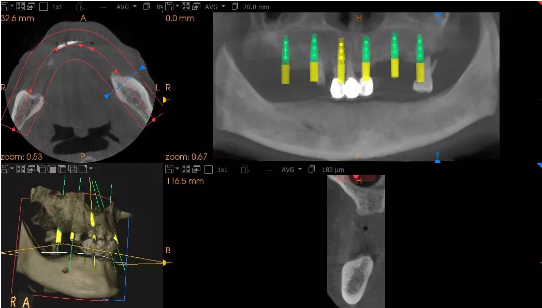

患者术前模拟方案

患者术后口腔全景片-上颌种入6个种植体